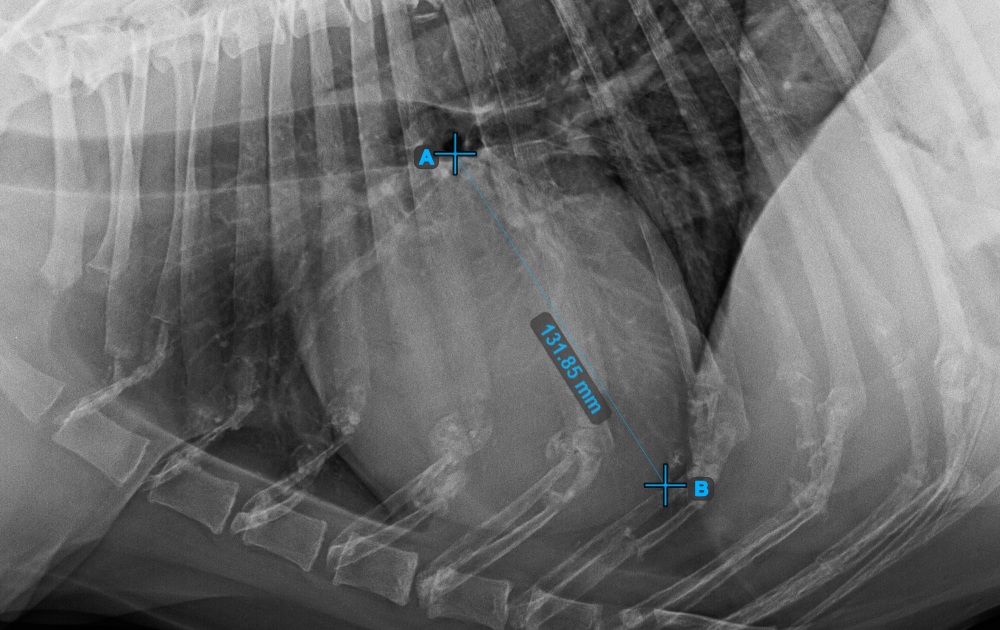

Complete the long axis of the heart by marking the Apex point, near the bottom of the heart.

The image below represents a typical placement of the Apex point.